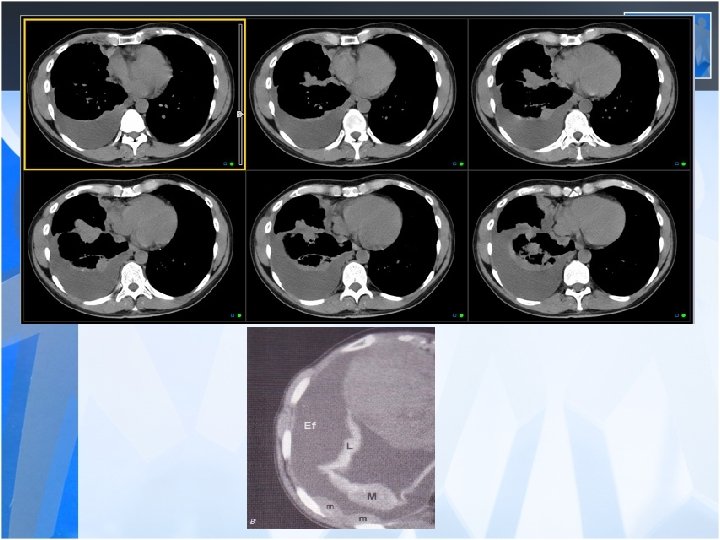

Pleural effusion • Benign pleural effusion – – Latent period 10 -20 years Exudative Asymtomatic Diagnosis by excluding other causes and history of exposure • Malign mesothelioma – The lifetime risk of developing mesothelioma among asbestos workers is thought to be as high as 10 percent. – There is a long latency of approximately 30 to 40 years from the time of asbestos exposure to the development of mesothelioma.

• The most common clinical presentations are dyspnea, chest pain, unilateral decreased volume of the affected hemithorax (frozen chest) • Nodular thickening of the pleura, irregular thickening of the interlobar fissure, absence of mediastinal shift with massive pleural effusion (frozen chest) • Diagnosis by histologic examination • Treatment oncologic and surgical if possible, prognosis is poor